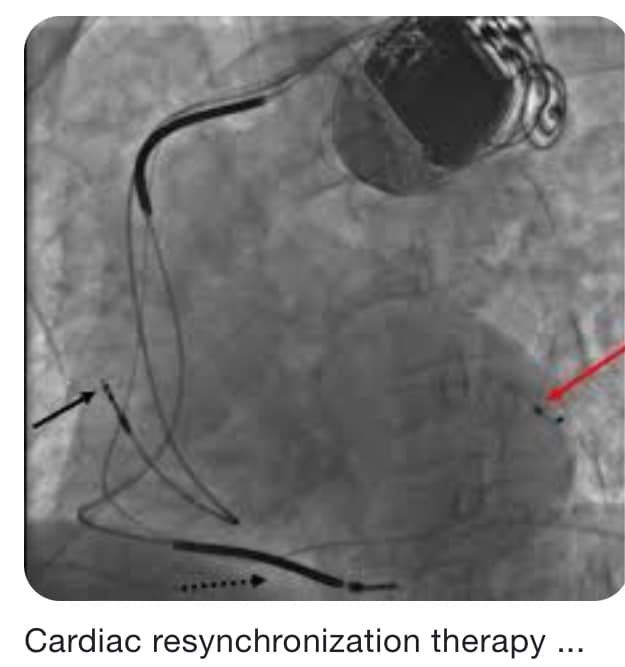

وتابع شعبان "زراعة الكابلات جوًا القلب لازم تبقي في نقط معينة وبتحتاج دقة رهيبة ومهارة عالية وتوفيق كبير من ربنا، واحد في الأذين الأيمن واحد في البطين الأيمن اللي طرفه عريض، ودا الكابل اللي بينقل الصدمة الكهربية واحد في الوريد الجيبي لتحفيز البطين الأيسر"

وقال "الجهاز دا بيعمل ربط كهربي وتناسق لكل حجرات القلب فتتحسن حالة القلب الانقباضية ويمنع تباطؤ القلب لو كهربا القلب الطبيعية ضعفت وفي نفس الوقت بيمنع بإذن الله الموت المفاجيء"